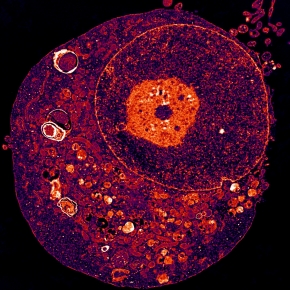

La cellule souche cancéreuse peut survivre en conditions hostiles notamment en atténuant les processus de dégradation intracellulaire médiée par les lysosomes.